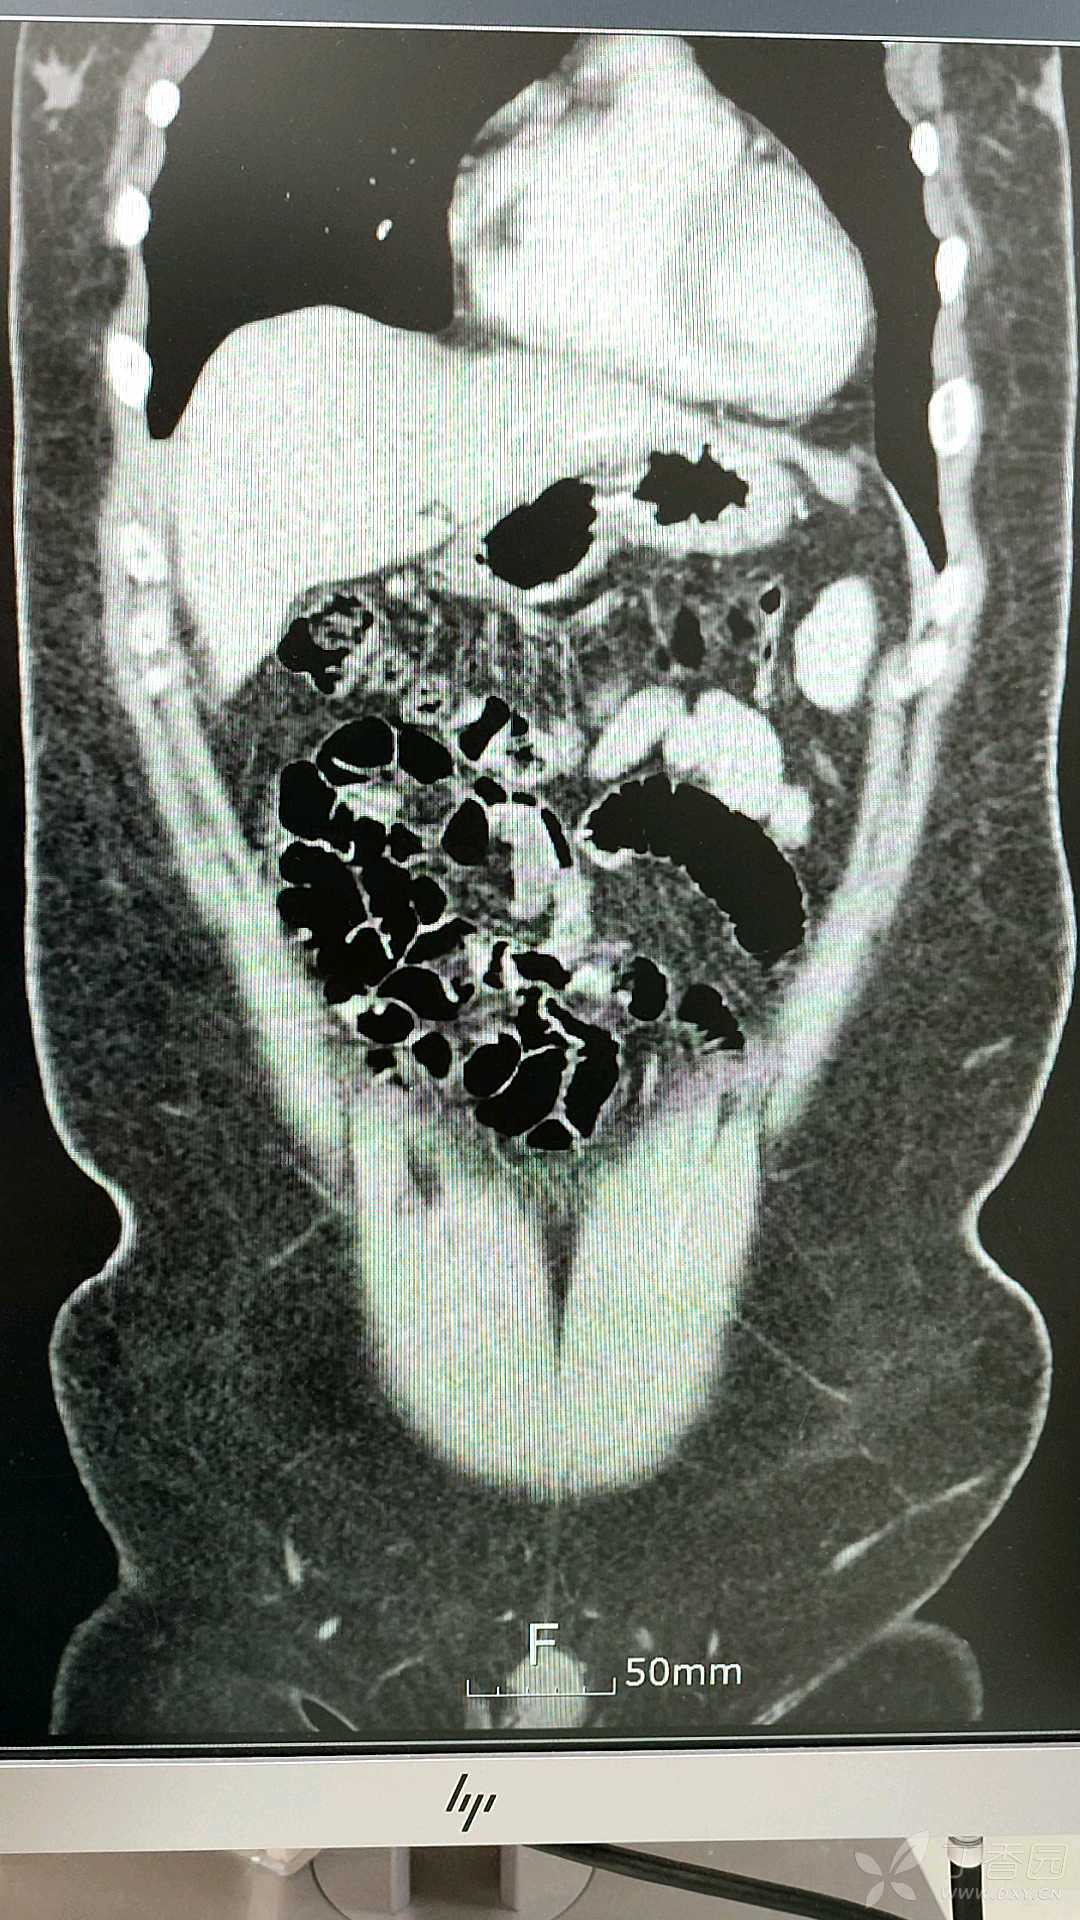

同门师兄,行胆囊摘除术后一个月,

仍然无法回到工作岗位,

进食过多,或荤腥油腻,

原胆囊部位,还是会疼痛。

CT如下: